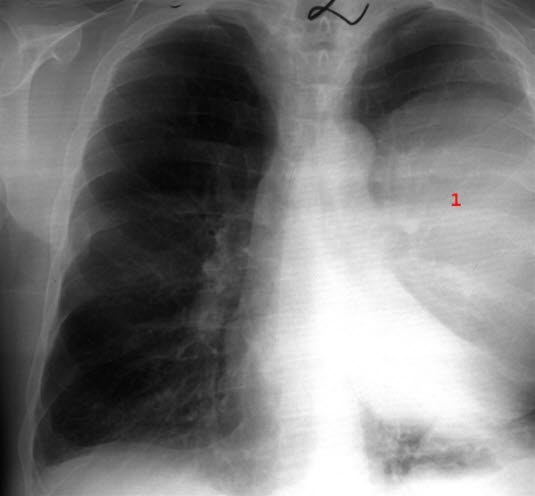

Lungeabscess - front

Lungeabscess, det vil si pussfylt hulrom i lungen (1)

Etter lungebetennelse